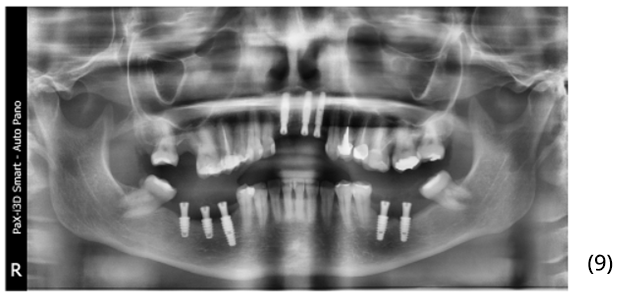

Após quatro meses, uma nova radiografia panorâmica foi realizada para planejamento reabilitador protético, onde nenhum sinal de anormalidade foi observado (imagem 9).